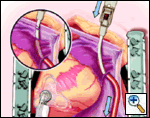

The plane between the LPA and LSPV is developed, and the large bronchus clamp is again passed from cephalad to caudad, with the tip of the clamp being seen caudal to the LIPV. The Robinson catheter is again used to isolate the pulmonary venous drainage on the left side, with the open end of the catheter again being cephalad.

Maintaining the same gentle curve in the clamp, the left-sided pulmonary vein isolation is carried out in a similar fashion to the right side.